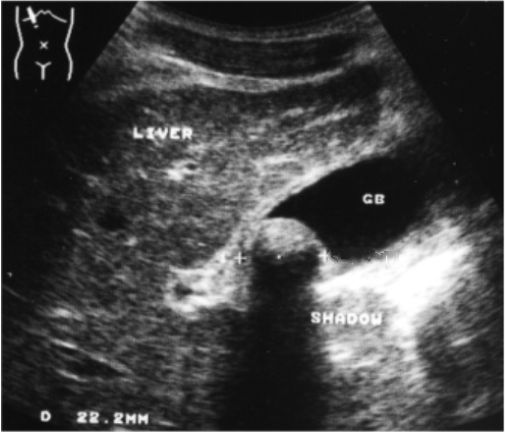

Examination

of

gallbladder

revealed

a

large

(2,2cm),

echogenic,

intraluminal

mass

with

smooth

surface.

broad

acoustic

shadow,

posterior

to

the

was

present.

wall

thin.

Rest

normal.

ANSWER:

Single

gallstone

in

gallbladder.